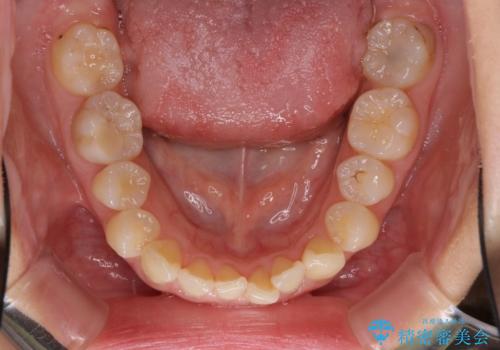

- 口元の深い咬み合わせ(ディープバイト)を気にして来院された患者様です。

インビザラインによる上下歯列の遠心移動(後方移動)により、口元のデコボコとディープバイトを改善することとしました。

下顎左右の犬歯とその後ろにある第一小臼歯、計4歯がシミュレーション通りに動かずディープバイトがなかなか改善されませんでした。

マウスピースの再製作を何度か行いましたがうまくいかないため、部分的にワイヤー矯正を併用することを提案しました。しかし、最も気になっていた前歯のデコボコはきれいに改善されたため、これ以上治療を希望されず、治療を終了することとしました。(今後気になった際には再開する予定です)